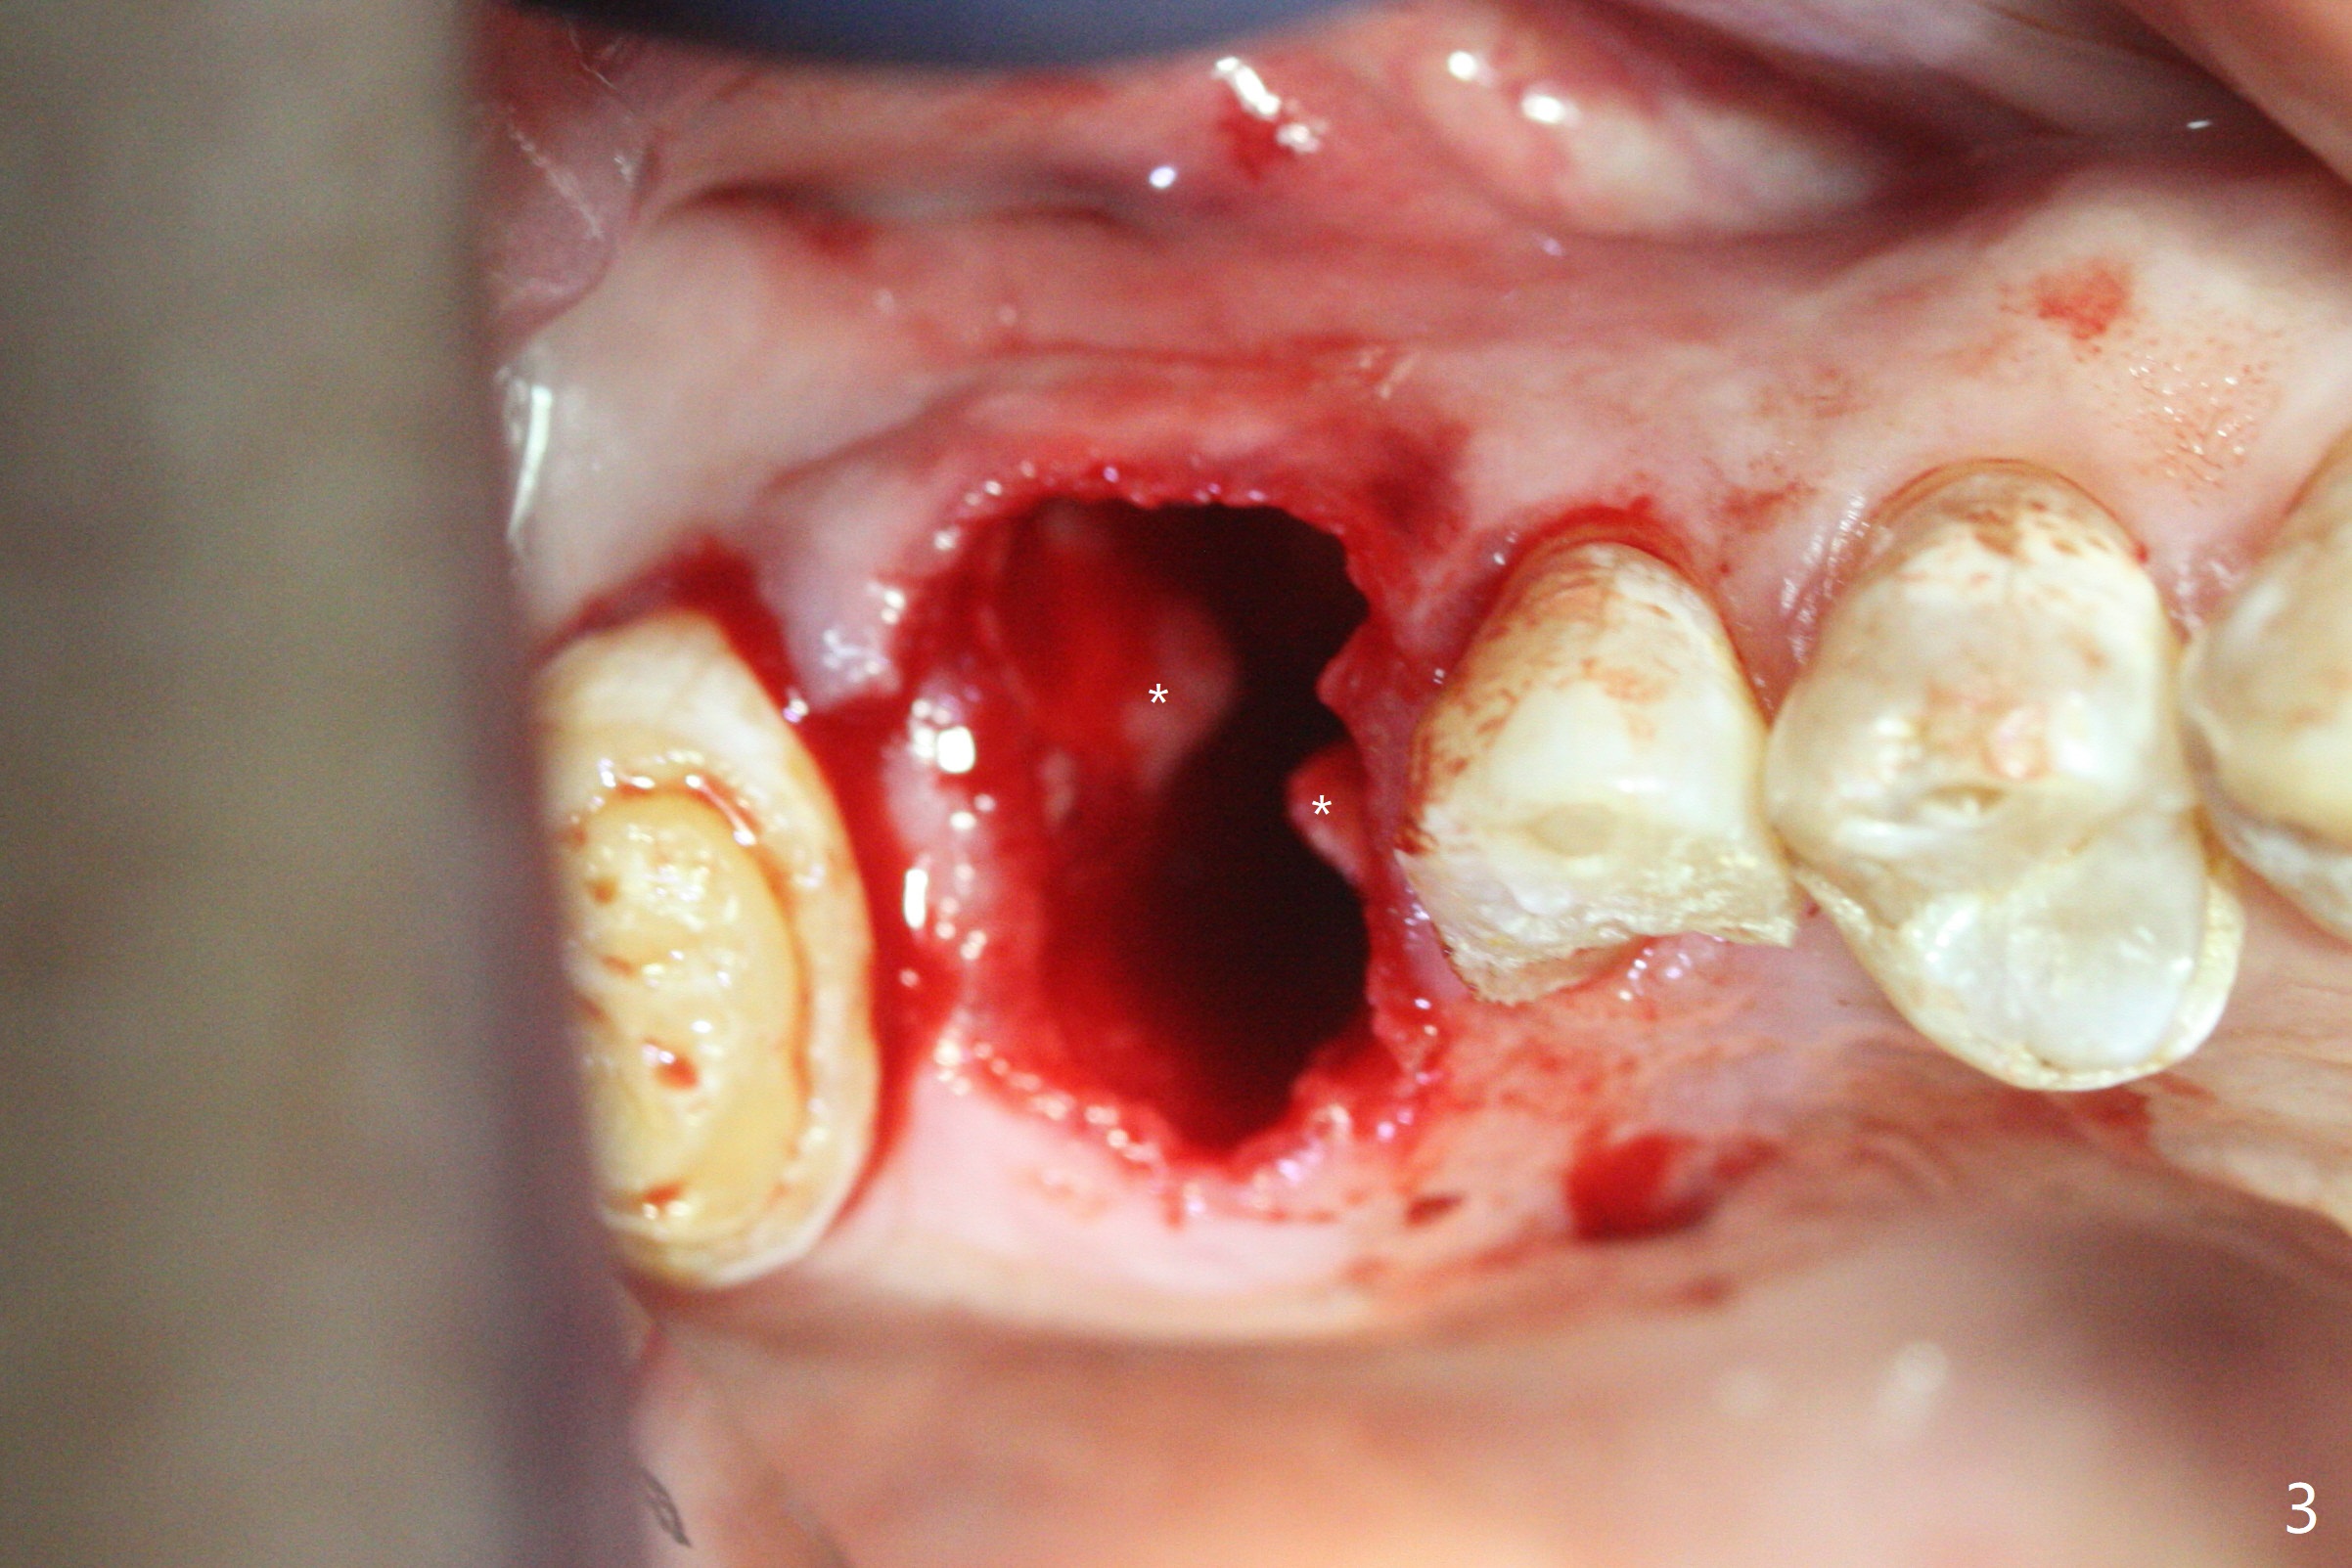

A 56-year-old man with signs of bruxism (multiple occlusal wear and tear, Fig.1) returns from an endodontist office because of failed RCT retreatment at #3 (Fig.2 (* palatal swelling; > fistula)). After difficult extraction, the socket is large without much septal bone (Fig.3 *). Because of lack of the apical native bone, immediate implant is not placed. If it has to be done, a large and long one is required. Instead socket preservation is finished (Fig.4 *). The socket is 20 mm deep, while the shank of surgical curettes is 20 mm. It appears that the most apical granulation tissue is hard to be removed. When 7-day oral Clindamycin is finished, the patient returns with chief complaint of recurrent pain and fistulae. In fact the palatal fistulae are flat without erythema. He returns asymptomatic 2 weeks postop; the fistulae are disappearing (Fig.5 ^) and the socket is healing (Fig.6).